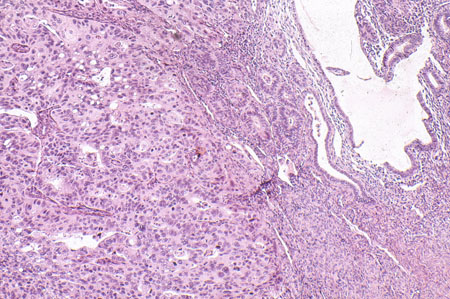

Grau 2 (G2): padrão de crescimento sólido não escamoso ou não morular de 6% a 50%

Grau 3 (G3): padrão de crescimento sólido não escamoso ou não morular >50%.[Figure caption and citation for the preceding image starts]: Adenocarcinoma endometrioide de grau 3 ou de alto grau com um histórico de endométrio atrófico (fotomicrografia, coloração de hematoxilina e eosina)Cortesia do Professor Robert H. Young, Departamento de Patologia, Massachusetts General Hospital [Citation ends].

Geralmente, G1 e G2 são baixos e G3 é alto.